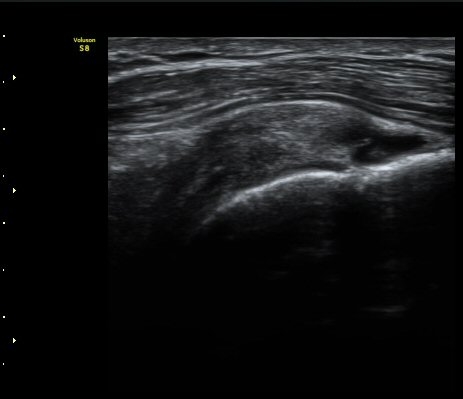

À̵ιڱ٠Á¾´Ü¸é°Ë»ç»ó ƯÀÌ ¼Ò°ßÀ» º¸ÀÌÁö ¾ÊÀ¸³ª(±×¸² 1)  ŽÃËÀÚ¸¦ ¾Æ·¡·Î À̵¿ÇÏ´Ï

°ß°©ÇÏ±Ù°Ç ³»Ãø¿¡¼­ ¼ö¾×Àú·ù°¡ °üÂûµÈ´Ù(±×¸² 2).